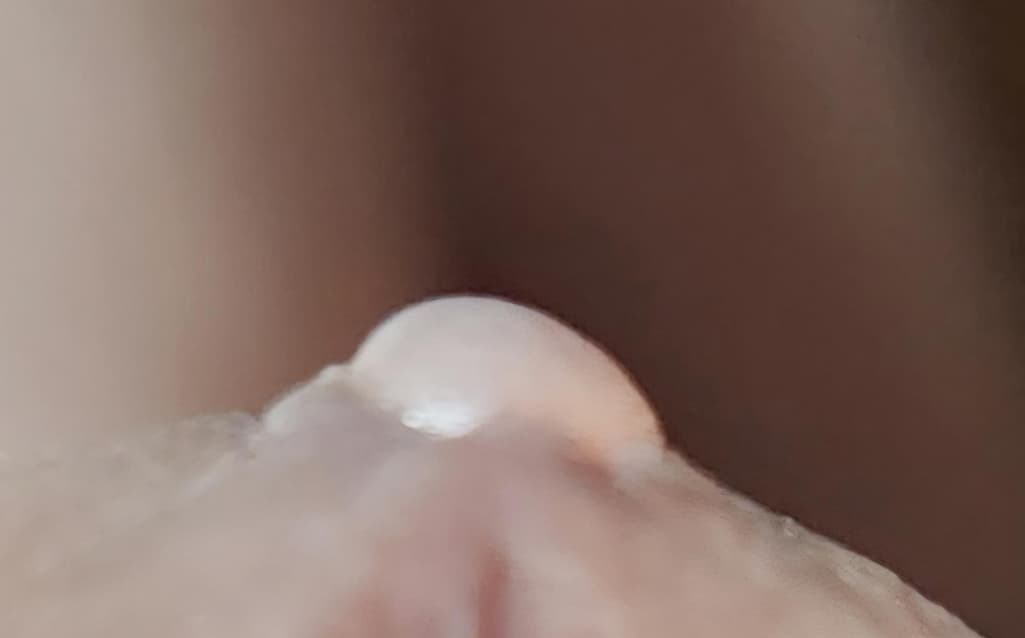

남성 성기 요도 밑부분에 물집 같은 거 하나 있더라구요

올려주신 사진상 작은 수포성 병변이 보이지만 헤르페스 감염과 같은 성매개성 피부 질환에서 관찰되는 다발성의 수포성 병변의 양상은 아닙니다. 헤르페스 감염의 경우 수포성 병변이 나타날 수 있지만 주변부 발적이 동반되는 경우가 흔한데 상기 병변은 수포만 단독으로 있어 외부 자극에 의한 마찰 등으로 인해 발생한 단독 병변 가능성이 높습니다. 통증이나 가려움이 었고 크기나 모양의 변화가 없다면 별다른 치료 없이 경과 관찰이 가능하겠으며 증상이 발생하거나 병변의 변화가 있다면 비뇨의학과 진료를 보시는 것을 권해드립니다.